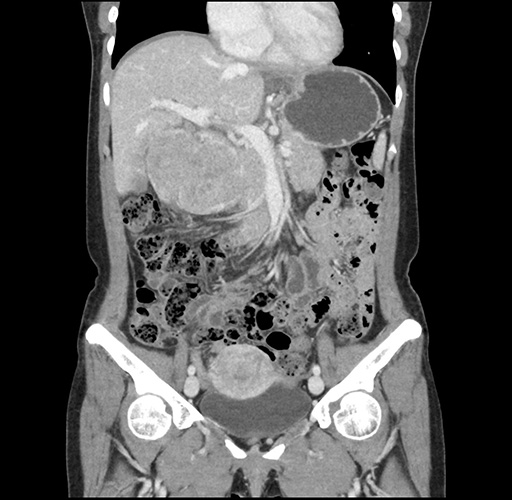

Imaging Analysis

Look through the patient's CT scan to identify any areas of concern for the necessary procedure.

Based on your CT findings, which issue(s) would give reason for "planned slowing down moment(s)" in this case?